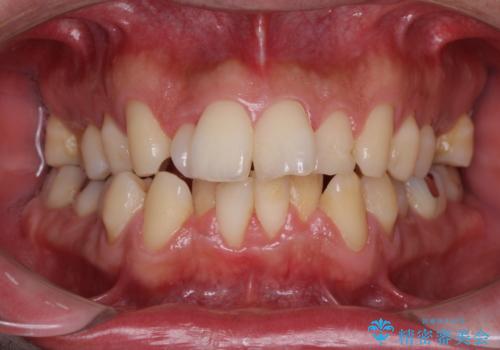

下顎骨が顕著に右側にずれている インビザラインによる咬合改善

- 上下前歯のデコボコを気にして来院された患者様です。

下顎骨が顕著な左右差を持って成長したため、右側にずれている状態でした。

デコボコは抜歯をすることなく解消できる程度であったため、インビザラインにより矯正治療を行うこととしました。